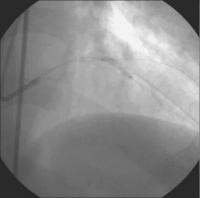

Sondierung - BMW-Führungsdraht

Abbildung 3: Sondierung beider Ästen mit je einem BMW-Führungsdraht (Guidant). Vordilatation des Ramus diagonalis mit einem 2,5 / 20 mm-Ballon (Hypro Pegaso, Sorin Biomedica) - 16 atm.

Keywords: KardiologieKoronarangiographieRamus diagonalis